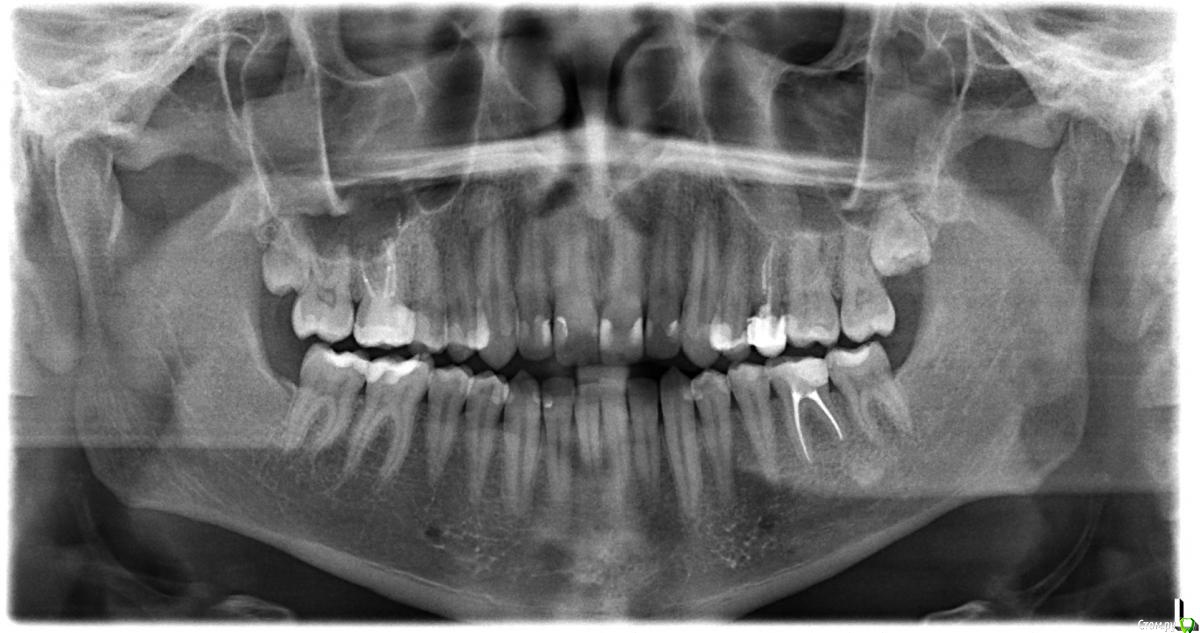

Falsecross Опубликовано 25 февраля, 2019 Поделиться Опубликовано 25 февраля, 2019 Здравствуйте. В 2017 г. была сделана микрогайморотомия с удалением кистогранулемы над 16-м зубом. Зуб был уже депульпированным. Спустя 4-5 месяцев начали проявляется странные ощущения в окружающих зуб тканях и губе, похожие на сокращение нервов или тики при давлении на верхушку 16-го зуба или небольшом давлении языком на него с внутренней стороны челюсти. Особенно отчетливо проявляется если надкусывать что-то жесткое этим зубом.В общем, это очень похоже именно на нервы. Будто под кожей или по десне "пробегают насекомые". Кроме того, когда зубной нитью прикасаюсь к десне между 16-м зубом и рядом стоящими, то тоже ощущаю что-то похожее на зуд. Пил финлепсин, колол лонгидазу и витамины B12 и B6 внутремышечно по рекомандациям лор-хирурга, но -- ноль реакции. Я изначально думал, что это нервы, попавщие в рубцы шва в месте проведения микрогайморотомии. Прошел уже множество врачей, от неврологов до ЧЛХ. Лишь ЧЛХ дал более или менее адекватные рекомендации -- удалить 8-ку, которая может давить на 16-й и 17 зубы, а также сделать пластику шва + пройти курс физиотерапии. Но сам врач делать что-то отказался, т.к. это все, с его слов, по профилю стоматологов. Также ЧЛХ препдположил, что виной всему может быть периодонтит. Собственно, именно к стоматологам с данной проблемой я не обращался. К какому конкретно врачу идти? Пародонтолог, хирург? Проводят ли физиотерапию в стоматологии и в каких случаях? Делают ли пластику швов после микрогайморотомии в стоматологии?Или же, может быть, стоит сразу идти к обычному физиотерапевту? Но будет ли физиотерапевт что-то делать без конкретного диагноза? Ссылка на комментарий

Falsecross Опубликовано 25 февраля, 2019 Автор Поделиться Опубликовано 25 февраля, 2019 КТ, конечно, есть. Загружу как доберусь до него. Однако, ни один врач ничего там не увидел. Ни ЛОРы, ни ЧЛХ, ни неврологи. Все говорят, что операция сделана хорошо. Ссылка на комментарий

Falsecross Опубликовано 27 февраля, 2019 Автор Поделиться Опубликовано 27 февраля, 2019 (изменено) Последнее КТ -- https://www.dropbox.com/s/5fo19o1h1vgmlrp/kt_chlh.zip?dl=0Не думаю, что кто-то будет заморачиваться с просмотром, но мало ли. неврологию никто не предполагал? Все предполагали, но неврологи разводят руками и отправляют к ЧЛХ. Это замкнутый круг. Очевидно, что с нервам проблема. Нужна физиотерапия, как минимум. Вопрос в общем-то простой. В стоматологии есть ли врачи, которые могут данной проблемой заняться и предложить решение в виде лечения? Делают ли физиотерапию в стоматологических клиниках? Вопрос, как такой врач называется, к кому идти? Изменено 27 февраля, 2019 пользователем Falsecross Ссылка на комментарий